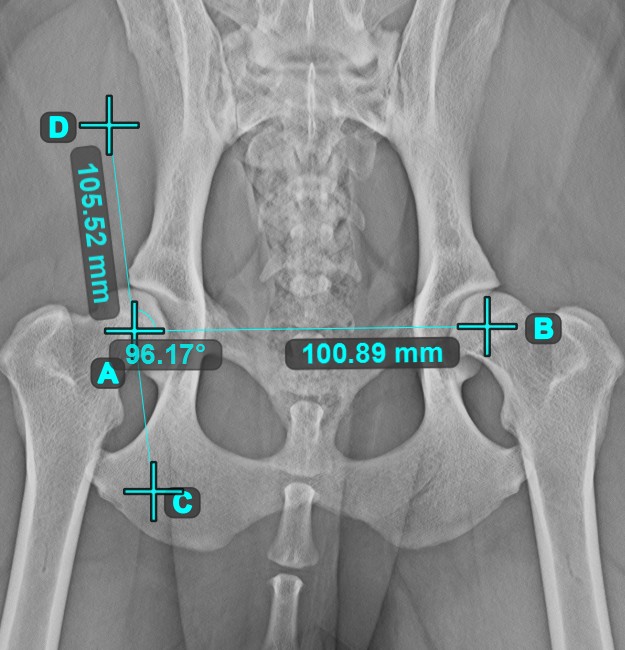

Angle of Lines¶

Select the tool from the left toolbar and assign it to one of the available mouse buttons. Start by selecting the first line from the ones already drawn on the scene, or place the start and end points to create the line. Follow the same steps for the second line of the measurement. The angle between the two lines will be automatically calculated.

Modify the start and end points of both lines by using the Select/Move Item tool. The angle between the two lines will be automatically recalculated.

Information

If two lines do not intersect directly, the angle of their extended projections on the scene will be calculated.